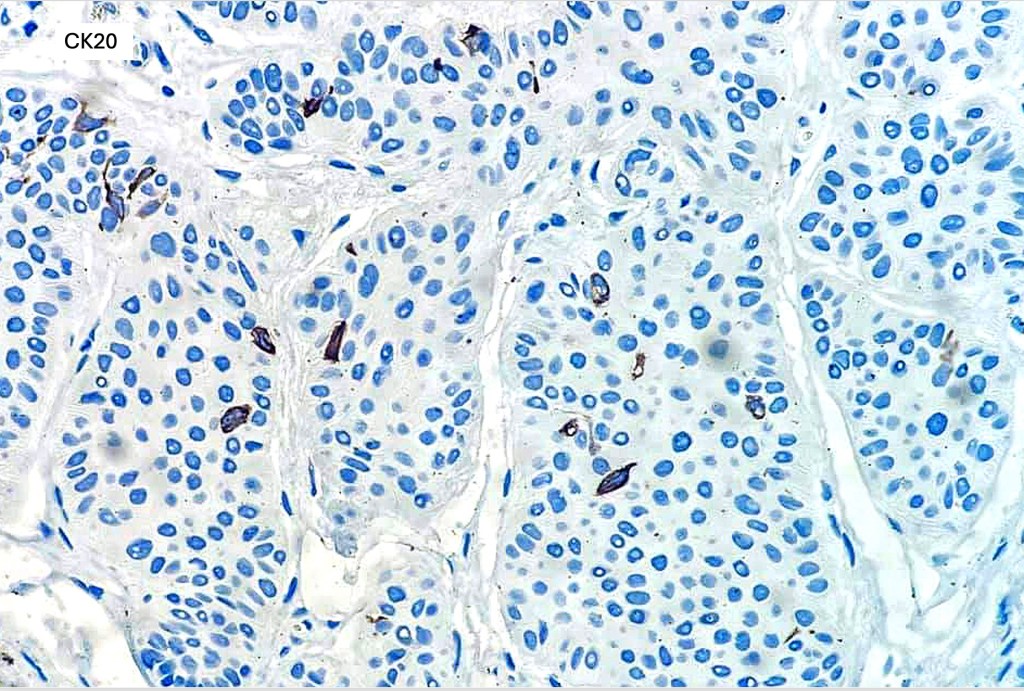

•CD20+ve Merkel cells